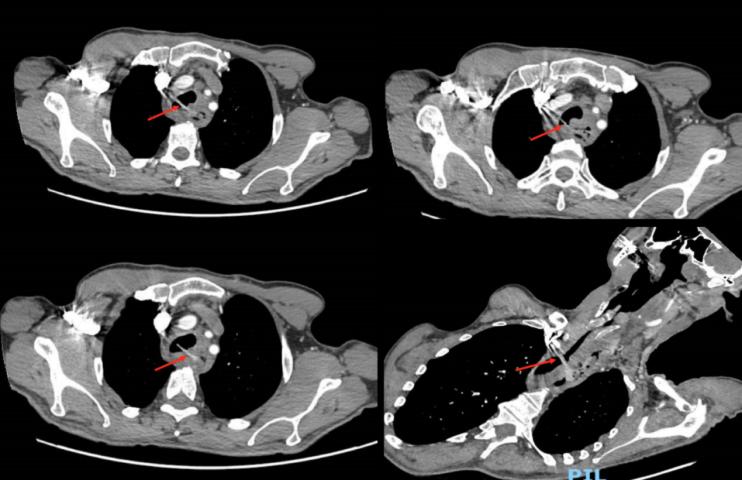

通过第四肋间右后外侧胸廓切开术进入瘘管部位。由于持续污染,纵隔发炎并纤维化,气管与食管紧密粘连。行气管切开术和取出义齿异物后到达瘘管(图3)。通过使用交叉通气,并在远端气管中放置气管内导管来维持气道。进行了气管切除术,切除了2cm的不存活气管组织,并对健康的近端和远端气管进行了端到端吻合。在吻合口上放置带蒂心包前脂肪贴片,以加强修复并促进愈合。食管在胸部被切开,近端被切开至颈部。在放置胸腔引流管后,关闭了胸廓。患者仰卧,颈部食管暴露在颈部左侧。由于气管和周围结构存在密集的纤维化粘连,近端食管的解剖较为困难。进行了颈部食管切除术。行经皮内镜胃造口术(PEG)以提供营养支持,在此期间,这是一种合适的肠内营养途径。

图3 取出的异物——可摘义齿